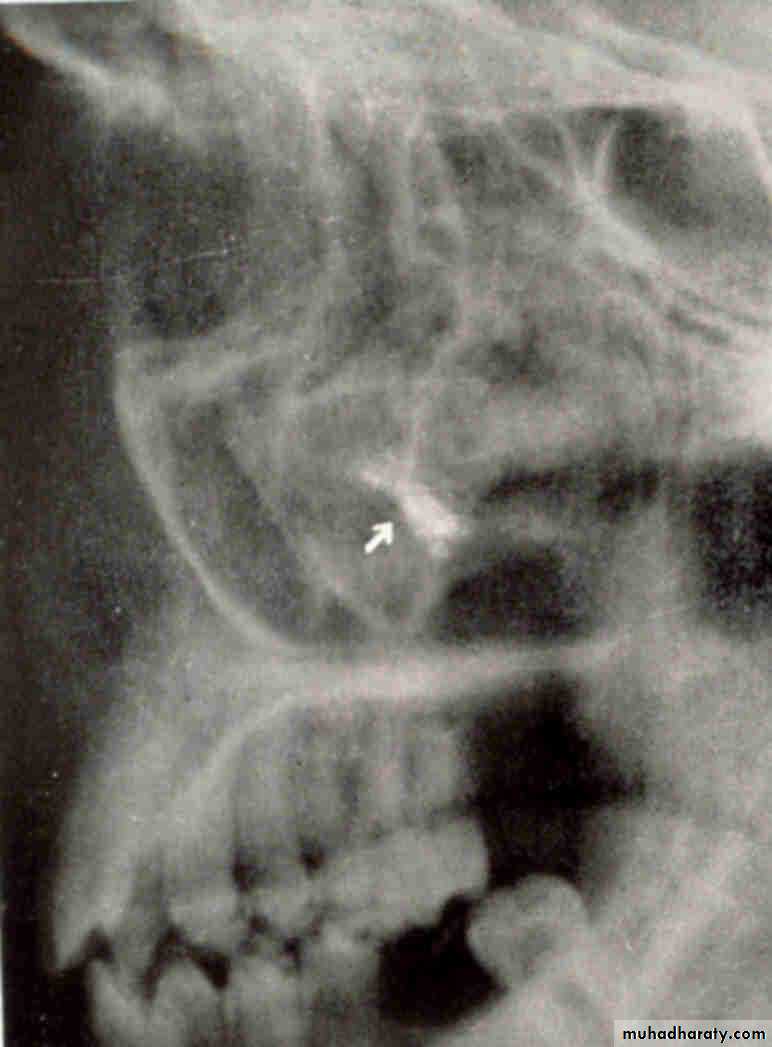

FISSURE BUR

FOREIGN BODYWATERS VIEW(Occipitomental )

LATERAL VIEWLateral oblique